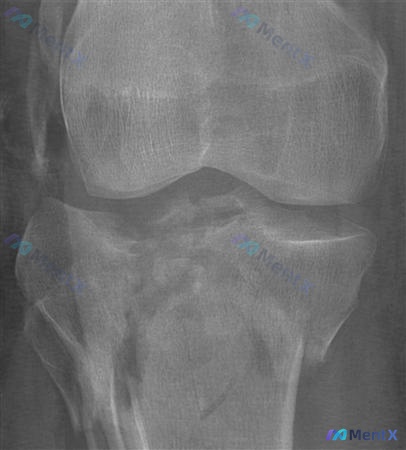

整理到一组关于胫骨平台骨折固定方式的影像资料和分析,有个点挺有意思: 题目问的是「哪张图用支撑板(支撑钢板)作为唯一治疗最有效」,给出的指向是图A; 但同时又有一段详细的影像描述:胫骨平台严重粉碎性骨折,外侧平台明显塌陷移位,关节面台阶感,伴腓骨近端骨折,力线改变。 如果只看这段文字描述的病例,大家...